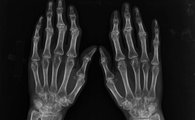

类风湿性关节炎是一种常见的风湿免疫病,该疾病除导致患者关节肿痛外,还极易致残。临床很多病人往往由于不了解类风湿病因,没能有效的预防,患病后得不到正确的治疗,拖延至晚期导致患者关节畸形,甚至丧失活动能力。

如何确诊患上类风湿性关节炎